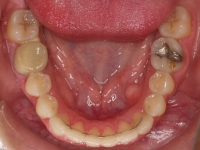

Premolar mandibular incluido + fenestración

45 incluido